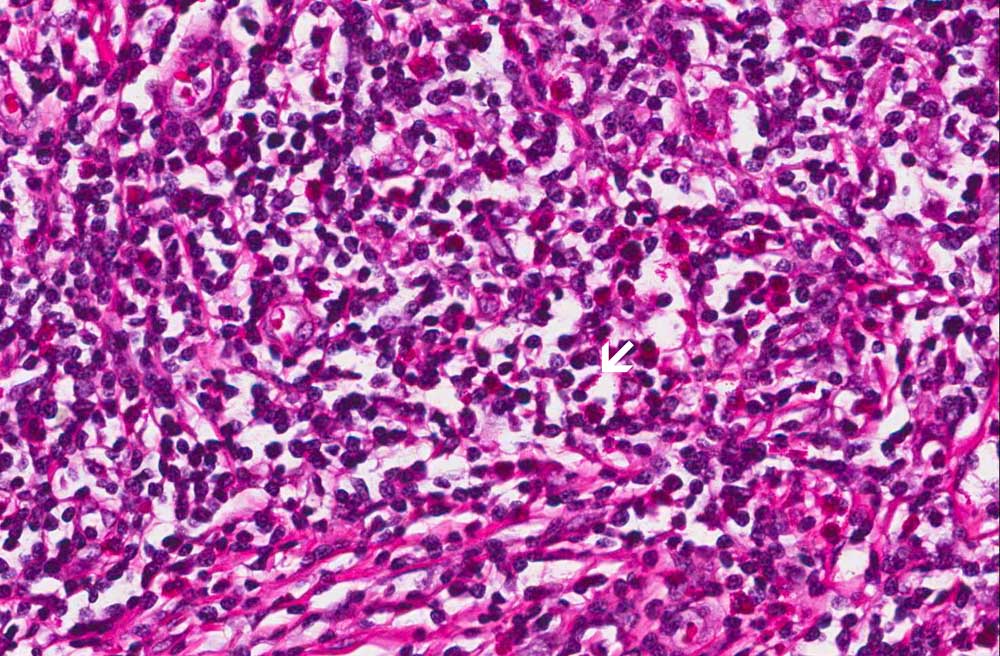

Area 2: Note that in this area, the large atypical cells are not readily seen. Many eosinophils (arrow) are present. This is often a suggestion but not a diagnostic feature of Hodgkin lymphoma.